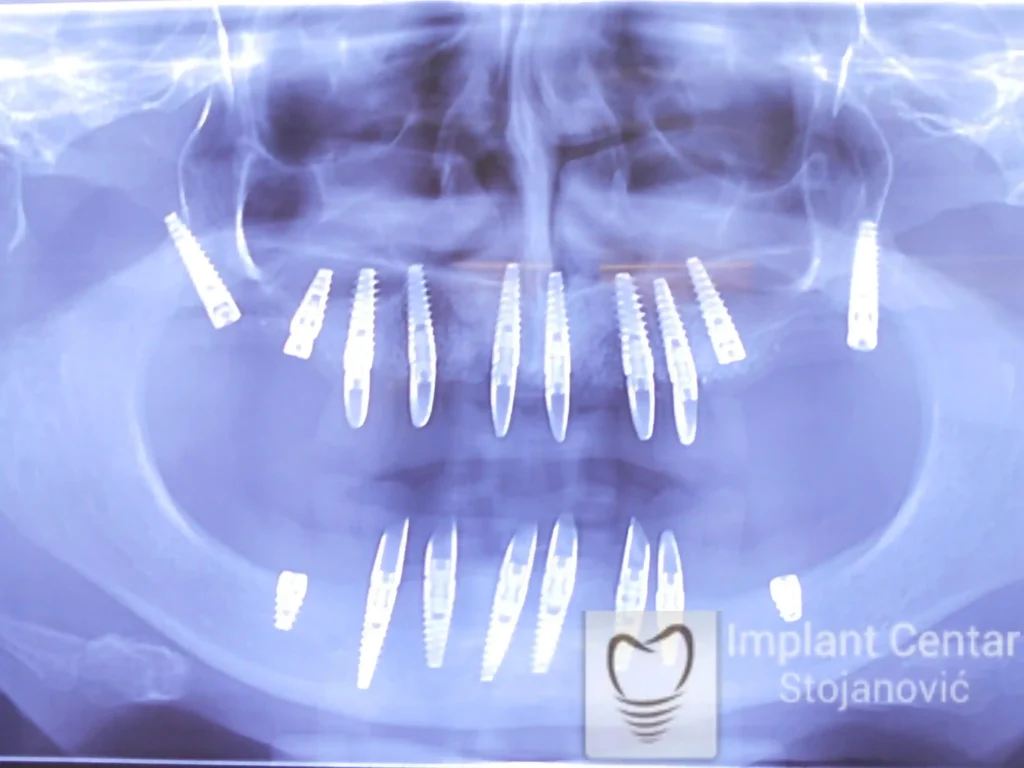

Zbog toga je plan terapije uključivao vađenje svih preostalih zuba i ugradnju implantata u gornjoj i donjoj vilici. U gornjoj vilici postavljena su i dva tuberopterigoidna implantata, kao zamena za sinus lift proceduru, što se može videti na ortopan snimku nurađenom odmah nakon ugradnje (slika 3).